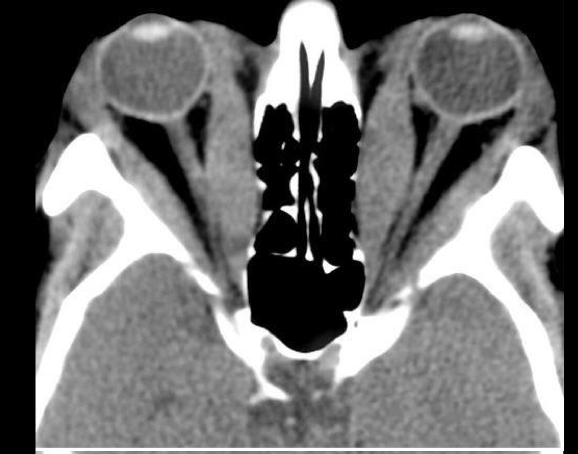

Q

A

TC en orbitopatia tiroidea

6